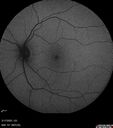

Central Retinal Vein Occlusion - Non-Ischemic - Excellent Outcome17 views57 year old man The right eye has had vision loss for about 3 weeks. He woke up with vision loss.

Medical Hx: HIV . Diabetes Mellitus (since 2014). Thyroid Disease.

Systemic Meds: gemboya. Metformin Hydrochloride. trulicity. losartan. vesepa. Synthroid .

VA OD: sc20/160 OS: sc20/20

TP: OD:14 OS:14

Treated with Avastin

VA 6 weeks later 20/32 – dry one shot.

Missed follow-up after second treatment and came 5 months later with good vision and no macular edemaAug 17, 2025